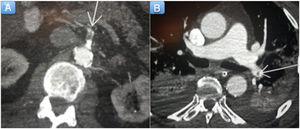

Se pautó tratamiento con doble antiagregación (ácido acetilsalicílico+clopidogrel) y anticoagulación con heparina sódica. Además, se inició tratamiento con hidroxicloroquina y tocilizumab. El paciente presentó evolución tórpida en las horas siguientes, con deterioro hemodinámico. Dada la mala evolución, se realizó tomografía computarizada toracoabdominal, en la que se observaron trombosis arterial en múltiples localizaciones con hallazgos compatibles con isquemia mesentérica (figura 2A), infarto esplénico y tromboembolia pulmonar del 28% (figura 2B). Finalmente, el paciente falleció transcurridas 72h de su ingreso.